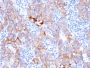

Recognizes a protein of 185 kDa, which is identified as c-erbB-2/HER-2/neu. Its epitope is localized in the extracellular domain. C-erbB-2/HER-2 is a member of the EGFR family. This MAb is specific and shows minimal cross-reaction with other members of the EGFR-family. Receptors of this family are located on the plasma membrane and consist of an extracellular ligand-binding domain that is connected to a large intracellular domain by a single transmembrane sequence. c-erbB-2/HER-2 protein is over-expressed in a variety of carcinomas especially those of breast and ovary. Primary antibodies are available purified, or with a selection of fluorescent CF® Dyes and other labels. CF® Dyes offer exceptional brightness and photostability. Note: Conjugates of blue fluorescent dyes like CF®405S and CF®405M are not recommended for detecting low abundance targets, because blue dyes have lower fluorescence and can give higher non-specific background than other dye colors.

Positive Control

SKBR-3 cells. Breast cancer tissues.

Tumor expression

Breast cancer|Ovarian cancer

IHC, FFPE (verified)

IHC (FFPE) (verified)